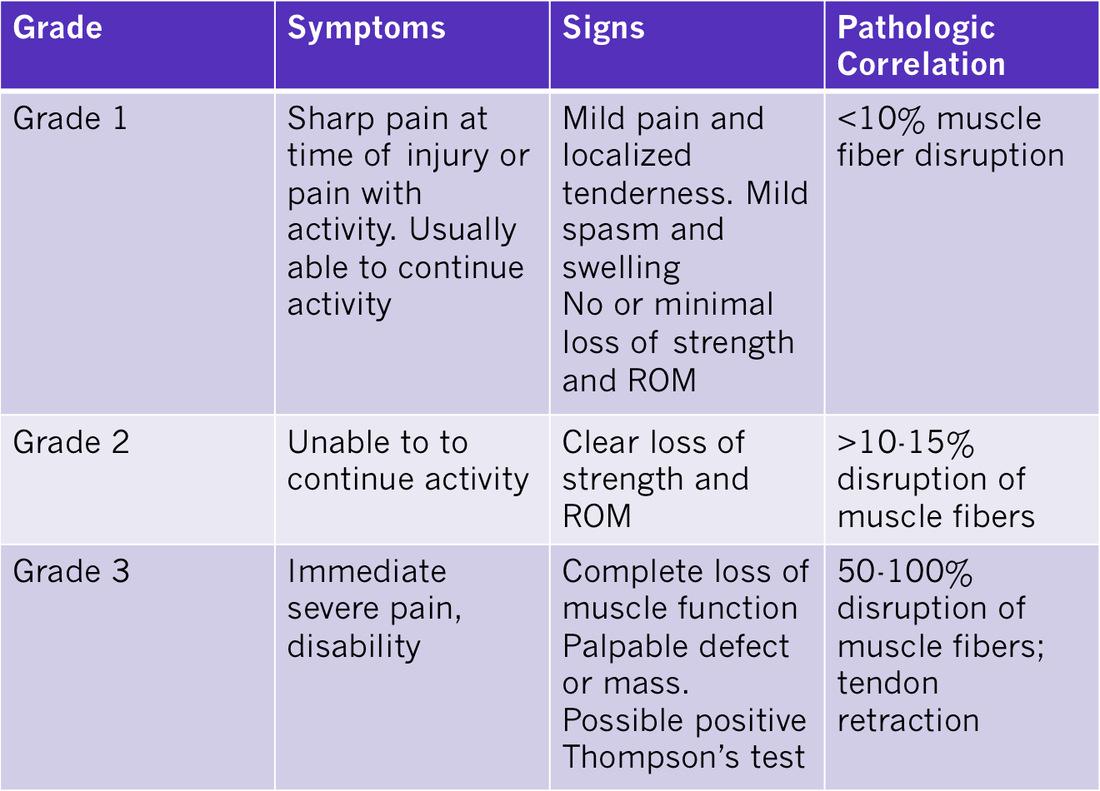

Gastrocnemius/Soleus Strain/Tear Differential Diagnosis of the Lower Leg